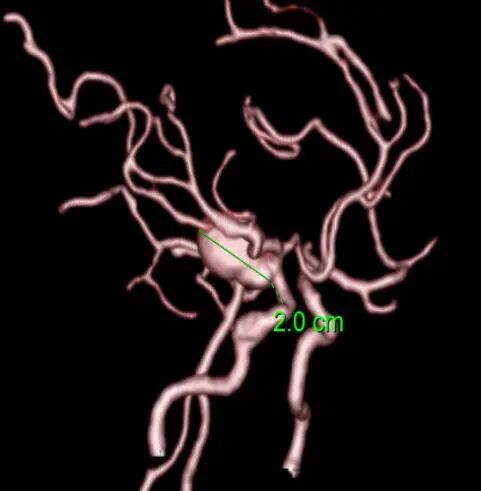

图片

动脉瘤腔内栓子形成后血流长径2cm